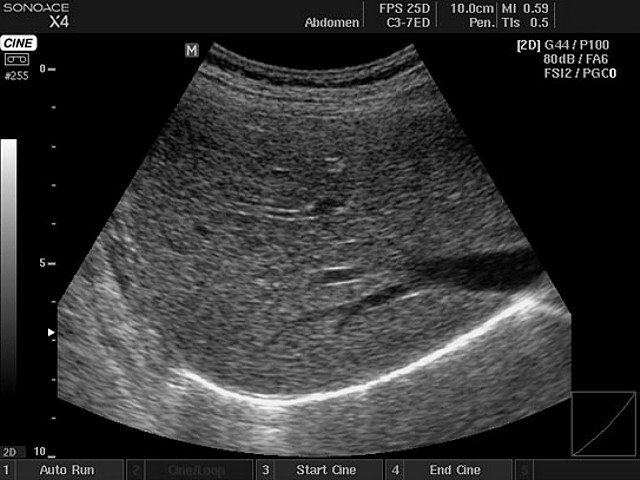

Le ecografie internistiche eseguibili in studio consentono di studiare fegato, pancreas, milza, reni, vescica, prostata, tiroide, testicolo, cute e sottocute.

Le ecografie vascolari eseguibili in studio consentono di studiare le arterie carotidi (tronchi sovra-aortici) e gli arti superiori e inferiori (doppler venoso e arterioso) oltre all'aorta addominale.

L'ecografo adottato in studio è un Esaote MyLab Six, con modulo color-doppler